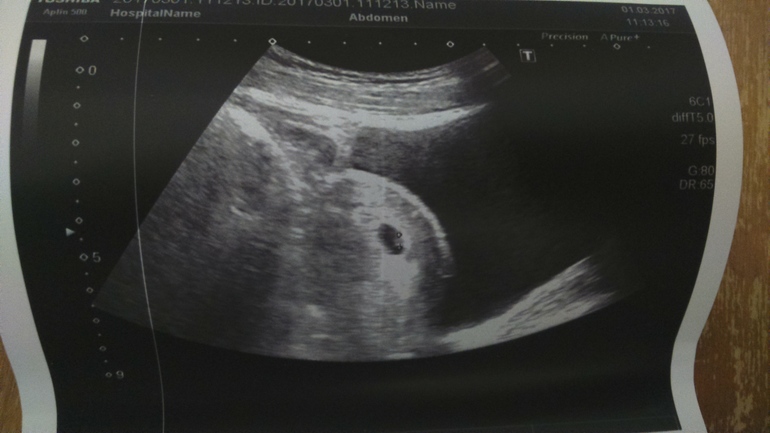

Результаты: УЗИ, КТГ, доплера, скринингаДевчонки,выручайте) срок по месячным 6 недель 6 дней) в среду на сроке 6 недель и 2 дня делала УЗИ(для своего спокойствия на работе) так вот) все вроде бы хорошо,плодное яйцо подросло 5 мм в нем эмбрион 3,8мм и бьется сердечко!) я плакала от счастья) но! Меня беспокоит,что кроме сонливость и периодически больных сосков ничего нет! И в интернете еще начиталась,что плодное яйцо должно быть больше и что мы не соответствуем сроку. Не знаю что думать. Что вы подскажите?) Завтра иду вставать на учет. По идее ровно 7 неделек будет) фото УЗИ под кат)УЗИ не вагинальное,а по животику)